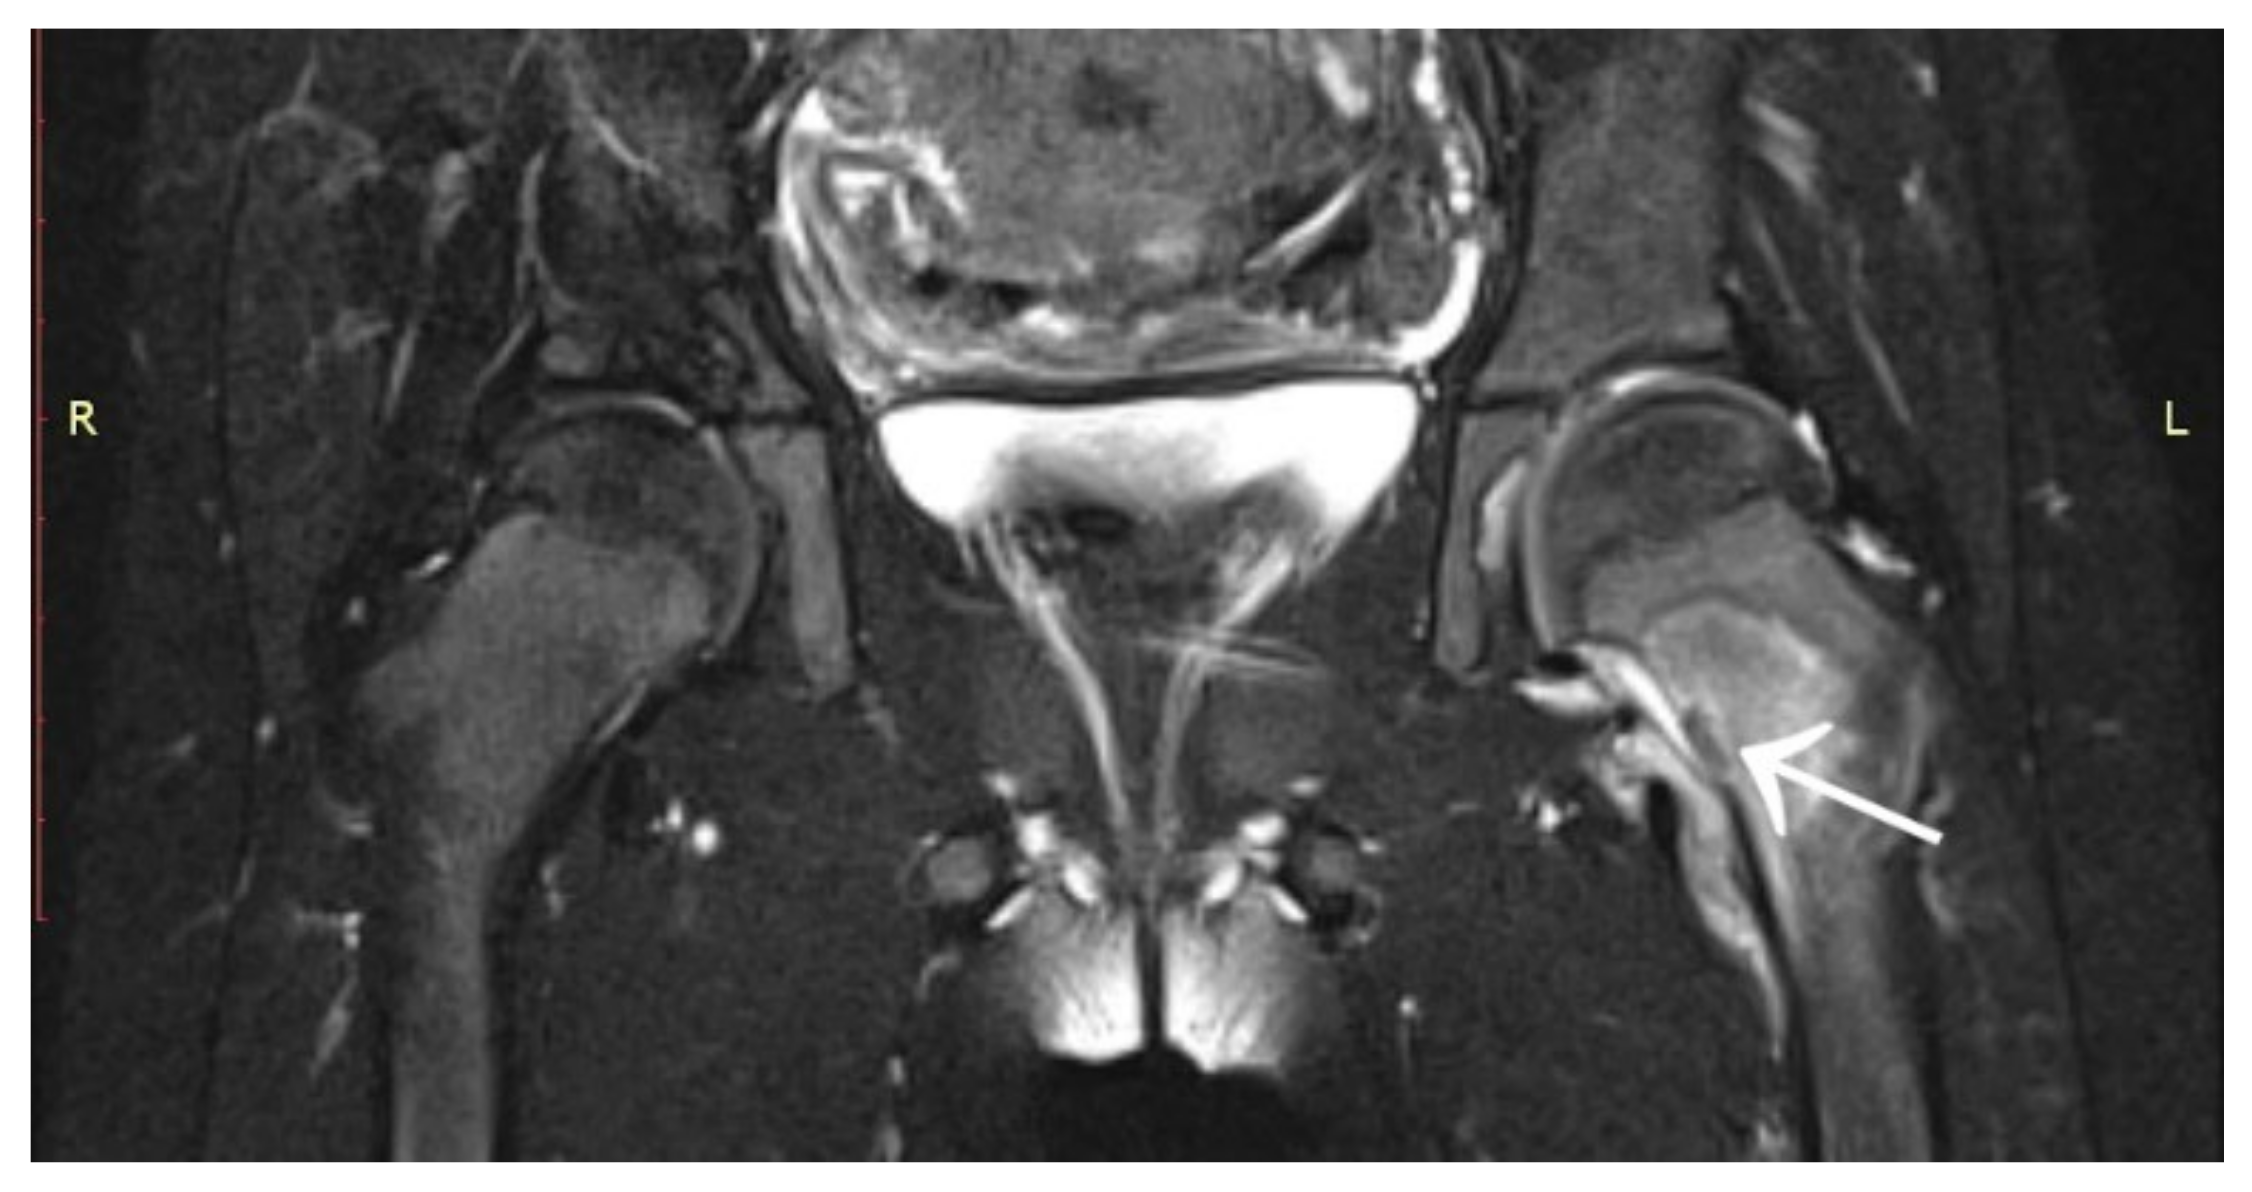

A 6-year-old girl was admitted to the Research Hospital of Orthopaedics for Children and Adolescents with symptoms of night pain (VAS score of 7), especially in the left knee, with lesser intensity in the left hip, accompanied by limping and decreased appetite. The diagnosis made six months earlier detected leucocytosis (23,000), positive IgM antibodies, and Western blot for Lyme disease. A diagnosis of Lyme disease was made, and the patient was treated with antibiotic therapy. The symptoms did not resolve after treatment. The patient underwent an MRI scan of the hip joints (Figure 5). Based on that examination, the patient was diagnosed with a left femoral neck stress lesion with a secondary fracture. The patient also underwent bone scintigraphy, showing a lesion in the left femoral neck (Figure 6). Persistent leucocytosis with the stimulation of granulocytes and features of abnormal cell maturation prompted a double bone marrow trephine biopsy and femoral biopsy. The image of the bone marrow ruled out proliferative disease in all cases. In the meantime, the patient’s emotional state deteriorated with depressive symptoms. The patient was treated by a psychologist with the diagnosis of a psychogenic component accompanying pain. As a result of a further exacerbation of the pain, the patient underwent a CT scan of the hip joints showing a 7 × 5 × 6 mm focus in the left femoral neck with a description corresponding to osteoid osteoma (Figure 7). Thermoablation with intraoperative 3D navigation was performed, resulting in the complete resolution of the symptoms (VAS score of 0 after 2 months).

Figure 5.

MRI scan showing a focus of OO (arrow) in the left femoral neck.